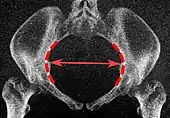

Conjugata vera as measured on sagittal MRI Low-dose CT scan of the transverse diameter of the pelvic inlet, as part of pelvimetry

Low-dose CT scan of the transverse diameter of the pelvic inlet, as part of pelvimetry Obstetric conjugate, as a measure of the pelvic inlet in the sagittal plane